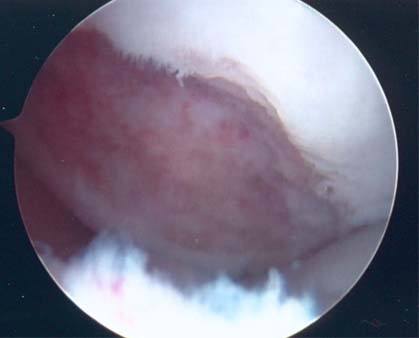

3.The arthroscopic views confirm a full thickness cartilage defect in the medial femoral condyle. The lesion is measured with a cut plastic ruler on the image on the right.

1. The arthroscopic photograph above shows a large cartilage defect in the end of the femur on the lateral (outer) side. The size of the defect measured 3.0 x 5.5 cm and involved the underlying bone.